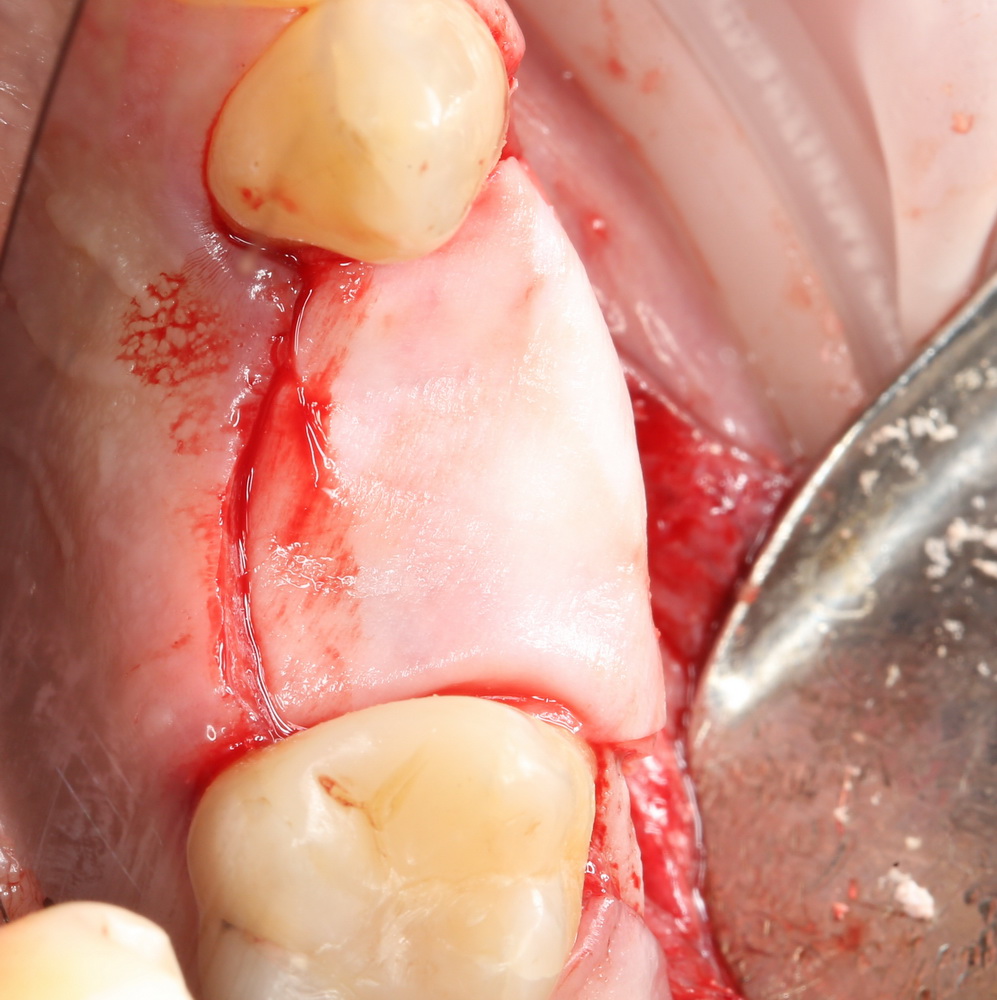

Другой вариант. Имплантируем, но существующего объема костной ткани недостаточно для получения адекватного эстетического и функционального результата:

Поэтому мы используем мембрану Geistlich BioGide и всё ту же аутокостную стружку:

Вот чем мне нравится мембрана BioGide — так это своими свойствами. Предсказуема до мелочей.

Во влажном состоянии она эластична и податлива, поэтому нет необходимости использовать пины или винты:

ну и, швы: